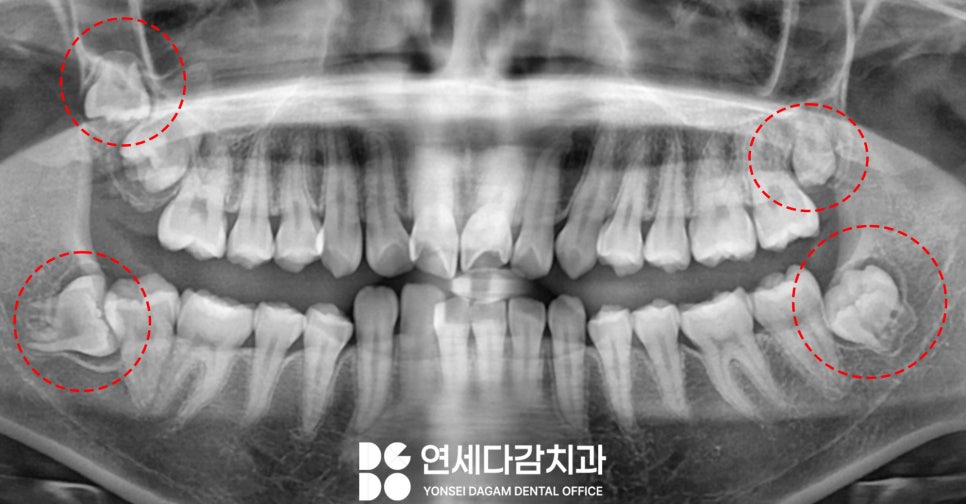

오금동 치과 에서 촬영한

파노라마 사진을 보면,

사랑니 4개가 모두

존재하고 있습니다.

해당 케이스는 교정 치료를 받을

예정이었는데요.

비발치 교정을 원하는 경우

치아를 뒤쪽으로 밀어서

공간을 만들곤 합니다.

그런데 사랑니가 있다면

치료에 방해가 되기 때문에,

이것을 해결하기 위해

맹출 되지 않았더라도

모두 빼는 케이스도 있습니다.

오금동 치과 에서는 교정 시작 전

하악 사랑니 2개를 먼저

빼는 것을 계획하였습니다.